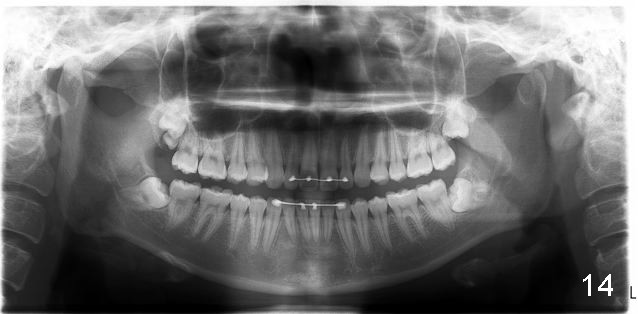

Why do the upper incisors need a lingual retainer?

Dr. Shaughnessy: Congratulation.  There is a supernumerary tooth coronal to #1.  Why do the upper incisors need a lingual retainer?

Answer: I was afraid tooth #8 would try to rotate (Fig.).  I do not like U bonded retainers as much as lower but I thought maybe in this case due to #8 initial position.  I have provided 2 removable retainers to fit over for insurance!

Excellent thinking.  According to the final photos, you must have done something to overcorrect the rotation of the two centrals.  Did you do it with purpose or by accident?  How did you do it, although Amy may not like it.  It seems to me that there is no practical way to overcorrect rotation.

Amy can floss with her retainer...